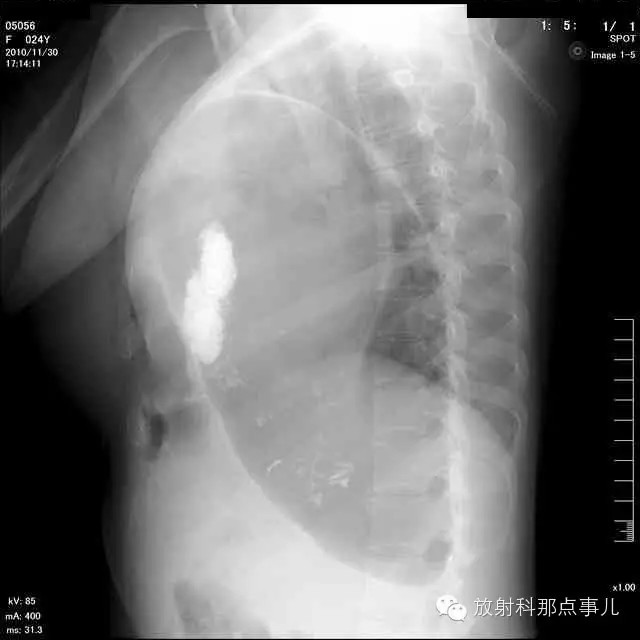

【病例学习】膈疝一例X线诊断

24岁,女性,腹痛渐加重并呕吐。

患者系顺产后18天产妇,产后感觉腹部疼痛不适,自认为正常反应,近两日因胸闷、腹部疼痛加剧伴呕吐来院就诊。

门诊腹部透视发现左侧胸腔巨大气液平面,为排除膈疝口服钡剂,但造影剂未见进入胃内。嘱住院,外科给予胃肠减压、补液等处理常规处理(未引流出明显气、液体)。5个半小时后再次检查,见少量造影剂进入消化道;为进一步了解情况,予泛影葡胺分别经胃管推注及口服,但均未进入胃内。当天进行外科急诊手术。

大部分胃、脾及横结肠均经过胸肋三角疝入左侧胸腔内,并见疝环形成。

考虑该患者因生产过程中腹压急剧升高,导致腹内脏器经膈肌缺损或薄弱部位进入胸腔内。